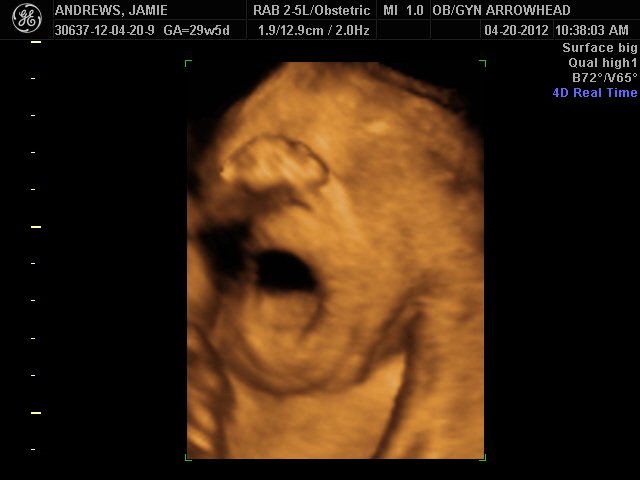

We offer complimentary 3D/4D Ultrasounds to all our OB patients around 30 weeks! The following photos are some examples of our work, shown with permission from our patients.